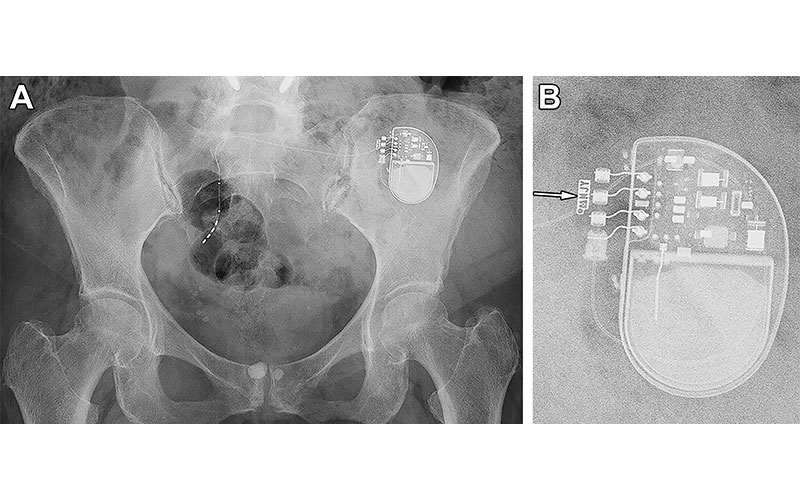

Radiographic identification of a sacral neurostimulator device in a 77-year-old woman. (A) Frontal projection radiograph of the pelvis shows a sacral neurostimulator device. (B) Magnified radiographic view of the device reveals the manufacturer symbol and identification code NJY (arrow), indicating that this device is a model 3058 InterStim II neurostimulator (Medtronic). https://doi.org/10.1148/rg.230102 © RSNA 2024